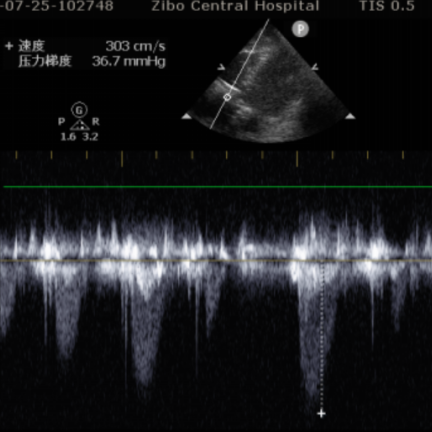

术前平均跨瓣压差36.7mmHg,左室射血峰值流速303cm/s,造影示明显反流。

超声示微量瓣周漏,患者血流动力学指标显著改善,植入后平均跨瓣压差5mmHg,植入后峰值流速1.5m/s。